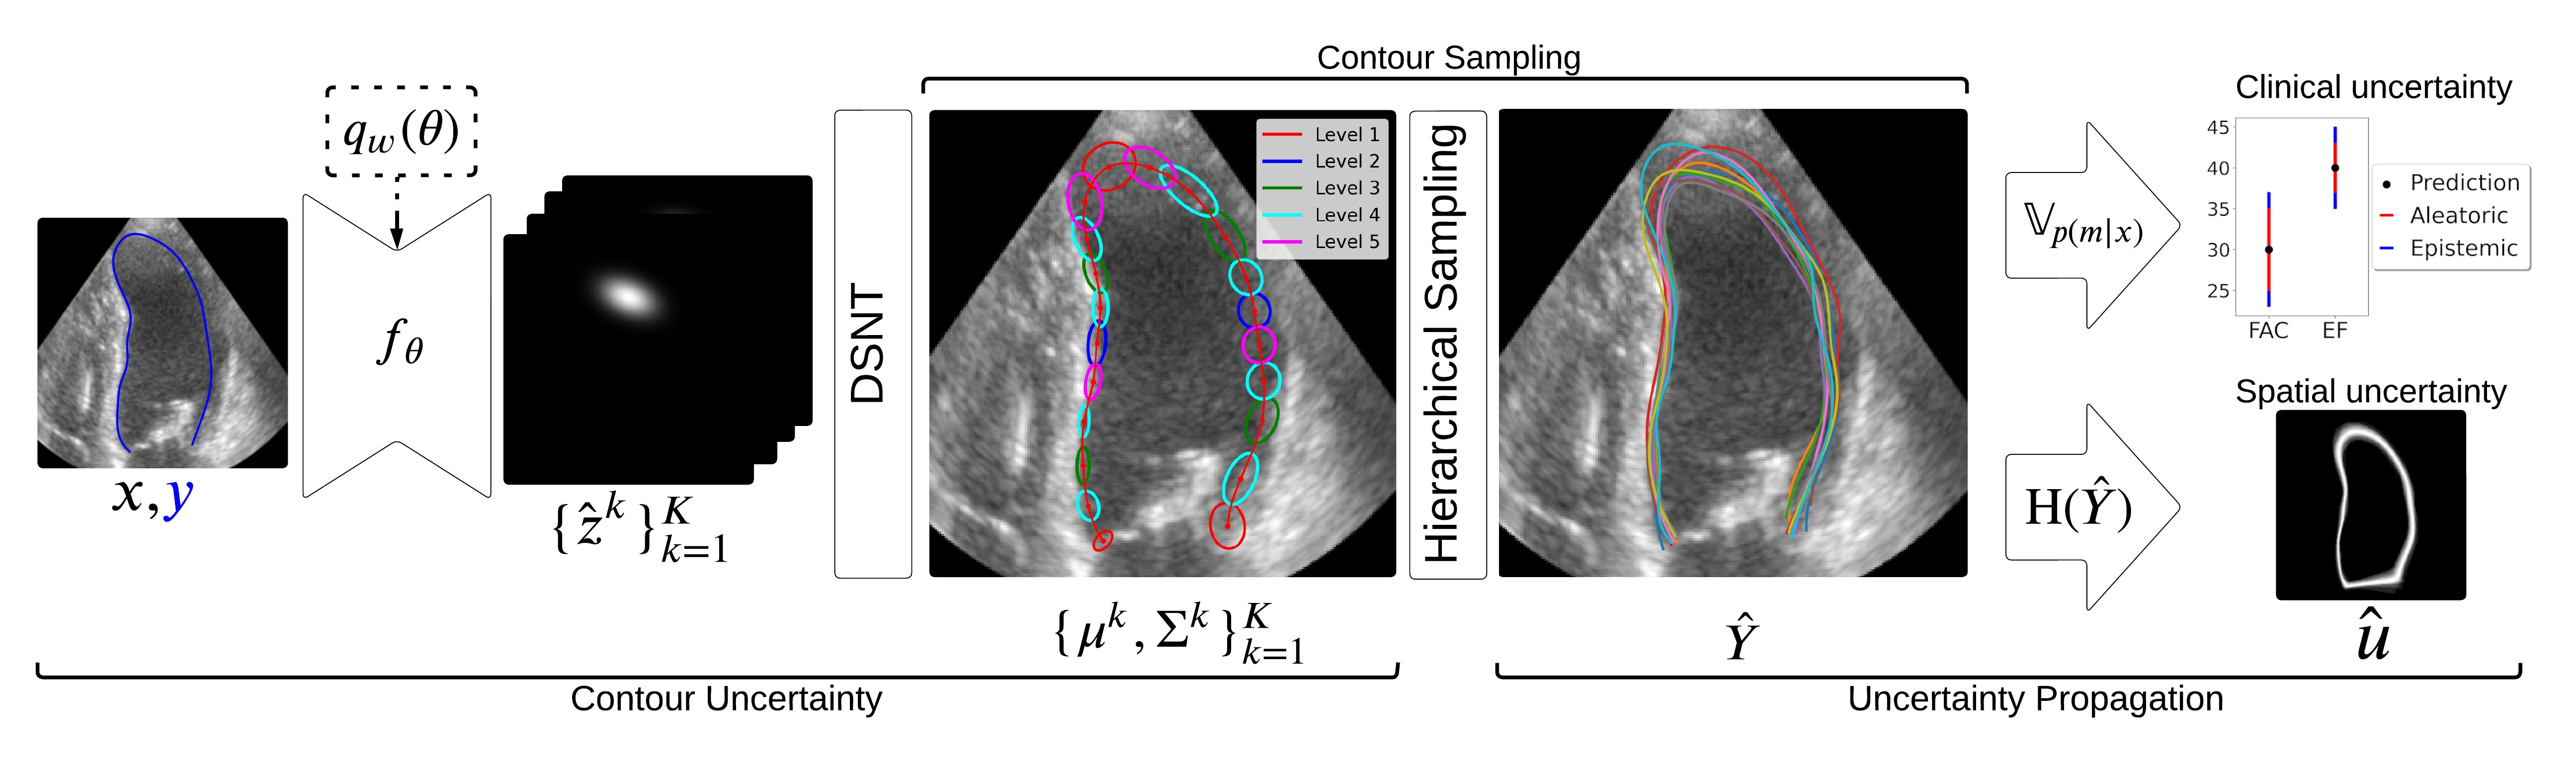

Uncertainty Propagation for Echocardiography Clinical Metric Estimation via Contour Sampling More Less

We propose a contour-based uncertainty estimation method for echocardiography that predicts uncertainty in heart boundary locations, samples possible contours from it, and propagates that uncertainty to clinical metrics like volume and ejection fraction.

Abstract

Echocardiography plays a fundamental role in the extraction of important clinical parameters (e.g. left ventricular volume and ejection fraction) required to determine the presence and severity of heart-related conditions. When deploying automated techniques for computing these parameters, uncertainty estimation is crucial for assessing their utility. Since clinical parameters are usually derived from segmentation maps, there is no clear path for converting pixel-wise uncertainty values into uncertainty estimates in the downstream clinical metric calculation. In this work, we propose a novel uncertainty estimation method based on contouring rather than segmentation. Our method explicitly predicts contour location uncertainty from which contour samples can be drawn. Finally, the sampled contours can be used to propagate uncertainty to clinical metrics. Our proposed method not only provides accurate uncertainty estimations for the task of contouring but also for the downstream clinical metrics on two cardiac ultrasound datasets.